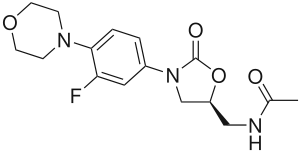

![Skeletal formula of N-{[(5S)-3-[3-fluoro-4-(morpholin-4-yl)phenyl]-2-oxo-1,3-oxazolidin-5-yl]methyl}acetamide, highlighting the morpholino and fluoro groups in orange, with the rest in blue. The carbon atoms of the parent chain are numbered.](../I/Linezolid_showing_oxazolidinone_pharmacophore.svg.png.webp)

The oxazolidinone pharmacophore—the chemical "template" essential for antimicrobial activity—consists of a 1,3-oxazolidin-2-one moiety with an aryl group at position 3 and an S-methyl group, with another substituent attached to it, at position 5 (the R-enantiomers of all oxazolidinones are devoid of antibiotic properties).[107] In addition to this essential core, linezolid also contains several structural characteristics that improve its effectiveness and safety. An acetamide substituent on the 5-methyl group is the best choice in terms of antibacterial efficacy, and is used in all of the more active oxazolidinones developed thus far; in fact, straying too far from an acetamide group at this position makes the drug lose its antimicrobial power, although weak to moderate activity is maintained when some isosteric groups are used. A fluorine atom at the 3′ position practically doubles in vitro and in vivo activity, and the electron-donating nitrogen atom in the morpholine ring helps maintain high antibiotic potency and an acceptable safety profile.[33][107]

The anticoagulant rivaroxaban (Xarelto) bears a striking structural similarity to linezolid; both drugs share the oxazolidinone pharmacophore, differing in only three areas (an extra ketone and chlorothiophene, and missing the fluorine atom). However this similarity appears to carry no clinical significance.[108]